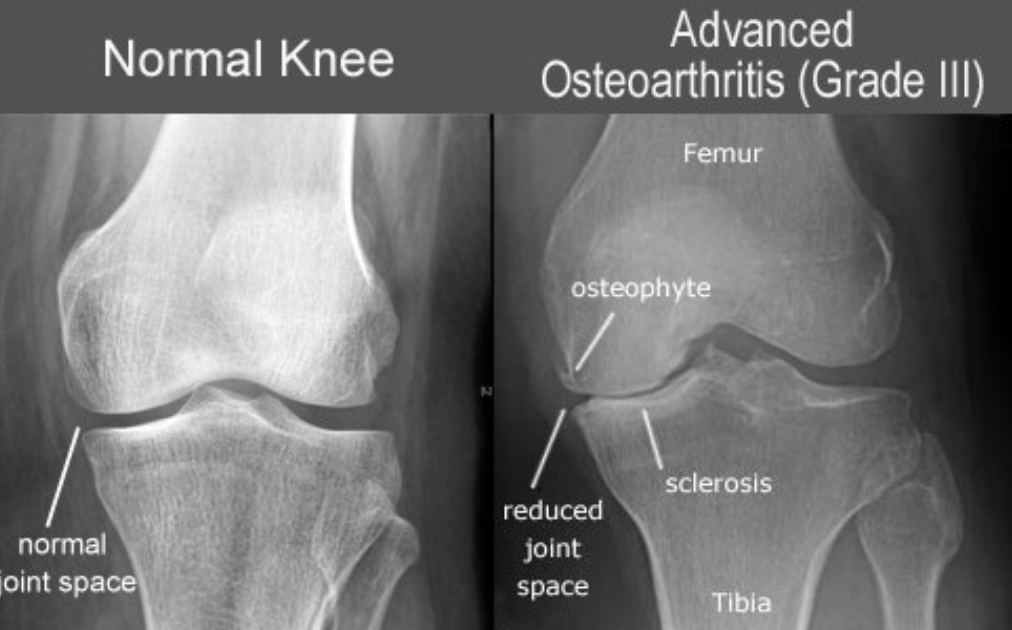

영상 검사

엑스레이로 관절 간격, 연골 소실, 변형 등을 확인하며, 필요시 MRI로 연골 및 인대 상태를 정밀하게 평가합니다.

관절염의 대표적 단계 구분은 켈그렌-로렌스(Kellgren-Lawrence) 분류를 통해 정해집니다.

♦ 주요 증상: 통증이 극심하며, 밤에도 불편, 뼈와 뼈가 직접 맞닿는 엑스레이 소견.